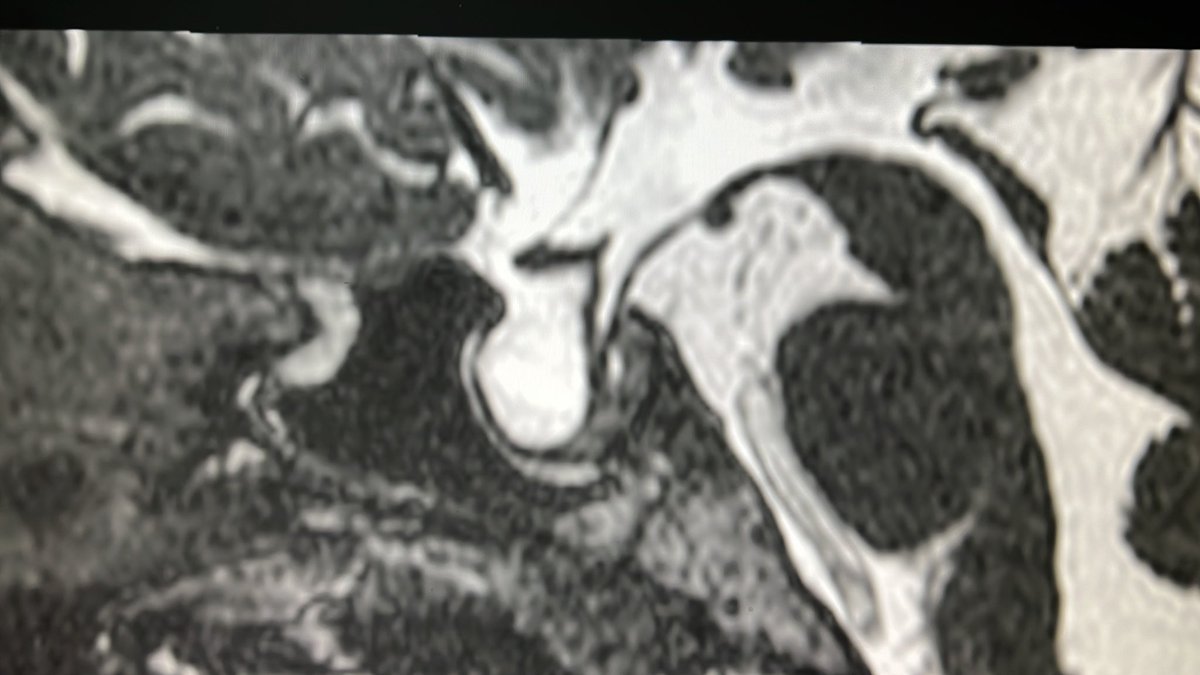

@drmankad

Dr Kish Mankad

2 years

Tip of the day šŸ’”: T2 hypo-intense core with peripheral ring enhancement are hallmarks of tuberculosis- even in this Caucasian child. With population movements, any disease can be found anywhere in the world without stereotypes. Travel with care this weekend.